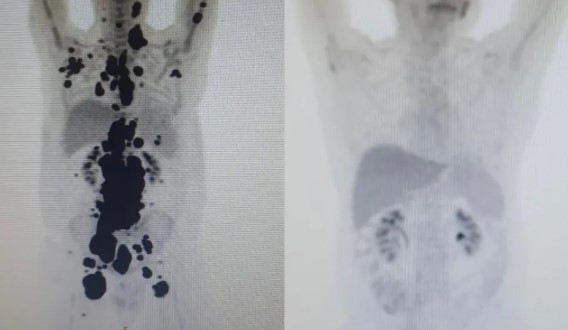

A Anvisa autorizou a Fundação Hemocentro de Ribeirão Preto (FUNDHERP), em parceria com o Instituto Butantan, a realizar o ensaio clínico no Brasil com o CAR-T Cell, a técnica que combate o câncer no sangue com as próprias células de defesa do paciente modificadas em laboratório. Oitenta e um pacientes passarão pelo estudo.

Segundo a Anvisa, os estudos estão em fase clínica inicial. O objetivo é avaliar a segurança e a eficácia no tratamento de pacientes com leucemia linfoide aguda B e linfoma não Hodgkin B, recidivados e refratários, em casos de reaparecimento da doença ou de resistência ao tratamento padrão.

Segundo Dimas Covas, à frente do estudo, nenhum paciente foi escolhido até agora. “O estudo agora vai definir a seleção dos pacientes. Inicialmente em Ribeirão Preto, depois São Paulo e Campinas”. Os pacientes precisam entrar em contato pelo e-mail: [email protected]

“A aprovação desse ensaio clínico é parte de um projeto inovador de colaboração regulatória entre a Anvisa e pesquisadores e desenvolvedores brasileiros. O objetivo é impulsionar o desenvolvimento de produtos de terapias avançadas disponíveis no Sistema Único de Saúde (SUS)”, escreveu a agência.